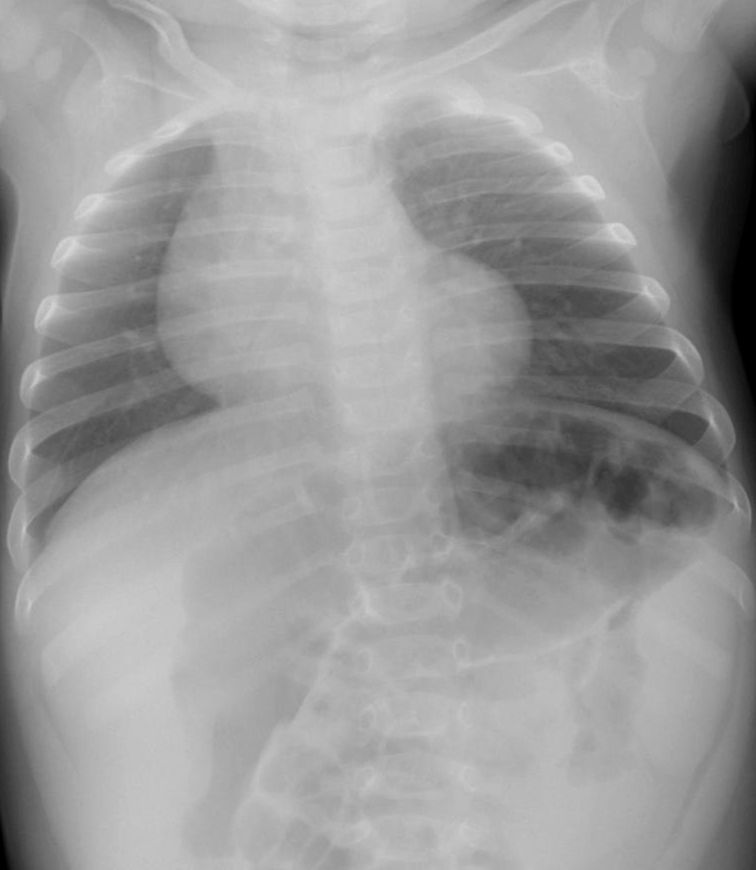

新生児・乳幼児によくみとめられるサイン。いずれも前縦隔にある胸腺を示している。胸腺は免疫器官として重要で、生後活発に活動しているため、この年齢では大きく、他の縦隔腫瘍と鑑別するのに役立つ。肋骨に圧迫されて波打つような形状がtjymic wave sign 、帆のように三角に突出してみえるのが sail sign 。

[参考例] ①透過性不良の間質性肺炎を示唆する写真だが、sail signをみとめる。同時に気管が右へ弯曲している。正面像で撮影できていないが、実際の臨床の場ではこのようなレントゲン像が少なくなく、読影に影響されてはいけない。 [参考例] ②右肺への張り出した陰影に肋骨部の凹みがあり胸腺と判断できる。 [参考例] ③縦隔の拡大があり右辺縁はwaveしていて胸腺と理解できる。(左肺野に浸潤影をみとめシルエットサイン陽性) [参考例] ④胸腺の典型例 epicardial fat(心臓横隔膜の脂肪組織) 心臓には脂肪組織が沈着していてレントゲン像として左右の心臓下部に均等な陰影として出現。右側には下大静脈の陰影もみとめるので銘記しておくとよい。 beginner’s triangle(正常でも異常に見えやすい右下肺内側のこと)(medicina Vol. 50 No.12 2013-11 一色論文 )。